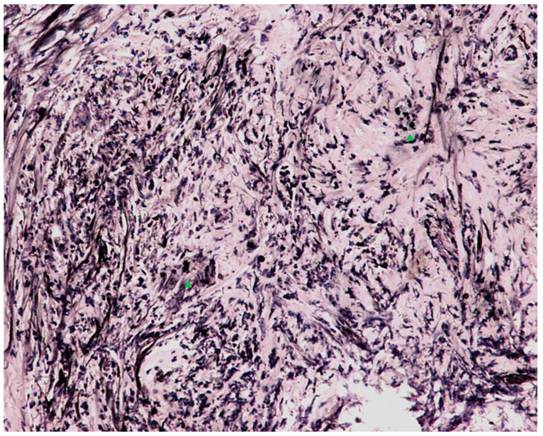

Fig 4

Microscopic examination with India ink staining (400x magnification). Numerous encapsulated yeast-like organisms measuring 7-10 μm in diameter were scattered in multinucleated giant cells (green arrowheads) and fibrous tissue throughout the entire CBD.

Next, following the operation, the blood, bile, sputum, CSF, urine and stool samples were cultured simultaneously with ink staining at least in triplicate. All samples were negative for Cryptococcus, but the final paraffin pathology of the intraoperative biliary samples confirmed the definite diagnosis. Microscopic examination demonstrated numerous encapsulated yeast-like organisms measuring 7-10 μm in diameter scattered in multinucleated giant cells and fibrous tissues throughout the CBD and gallbladder wall. The periodic acid methenamine silver stain, periodic acid Schiff stain and India ink stain were all positive (Fig. 4), whereas the pathogen identified by polymerase chain reaction from the paraffin-embedded gallbladder was Cryptococcus neoformans (VNI type1) [3]. As soon as she completed an uneventful recovery, she was transferred to the Gastroenterology Dept. again for anti-fungal therapy (beginning on POD11), an itraconazole regimen consisting of 2 weeks of inpatient intravenous injections (Sporanox® IV, Xian-Janssen Pharmaceutical Ltd., Beijing, China) followed by 10 weeks of per os outpatient therapy (Sporanox® Capsule). At two weeks after discharge (i.e., 4 weeks after starting the therapy), her transaminases had returned to normal levels, whereas TBil/DBil levels normalized after an additional 4 weeks. Moreover, her T-tube was removed after a cholangiography (Fig. 2B).